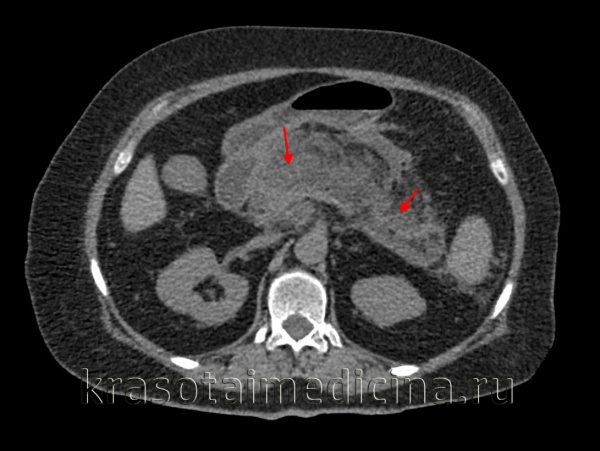

КТ органов брюшной полости. Панкреатит (в области хвоста поджелудочной железы) с наличием отека ее паренхимы, жидкостного содержимого вблизи ее края, на фоне утолщение фасции Героты слева

(Слева) На аксиальной КТ с контрастным усилением у пациента, злоупотребляющего алкоголем, определяется легкое повышение плотности перипанкреатического жира и отек, хотя поджелудочная железа не выглядит яв -но увеличенной в размерах. Эти изменения сопоставимы с отечным панкреатитом, протекающим в легкой форме.

(Справа) На аксиальной КТ с контрастным усилением у пациента после ЭРХПГ и установки стента определяется увеличение поджелудочной железы на фоне ее отека и потери нормальной дольчатой структуры, в сочетании с повышением плотности перипанкреатического жировой клетчатки и наличием жидкости около поджелудочной железы. Изменения сопоставимы с острым отечным панкреатитом. (Слева) На аксиальной КТ с контрастным усилением у пациента с жалобами на боль в животе определяется увеличение и отек поджелудочной железы с наличием жидкости возле нее и повышением плотности окружающей железу жировой ткани - изменения, сопоставимые с острым отечным панкреатитом. Все отделы поджелудочной железы накапливают контраст, признаки некроза отсутствуют.